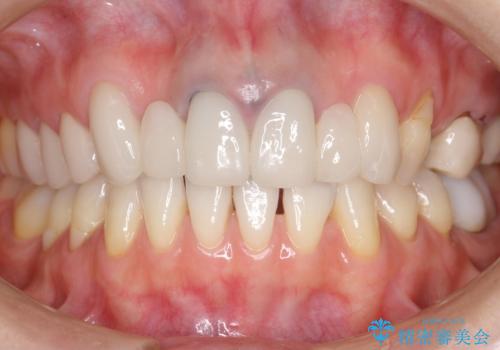

丁寧にう蝕除去と再根管治療を行い症状の改善を確認したのち、セラミッククラウン及びセラミックインレーによる補綴を行いました。

まるで天然歯のような自然な見た目と咬み心地にご満足頂けました。

気にされていた違和感もなくなり、喜んで下さいました。

クラウンの種類:オールセラミッククラウン スタンダード